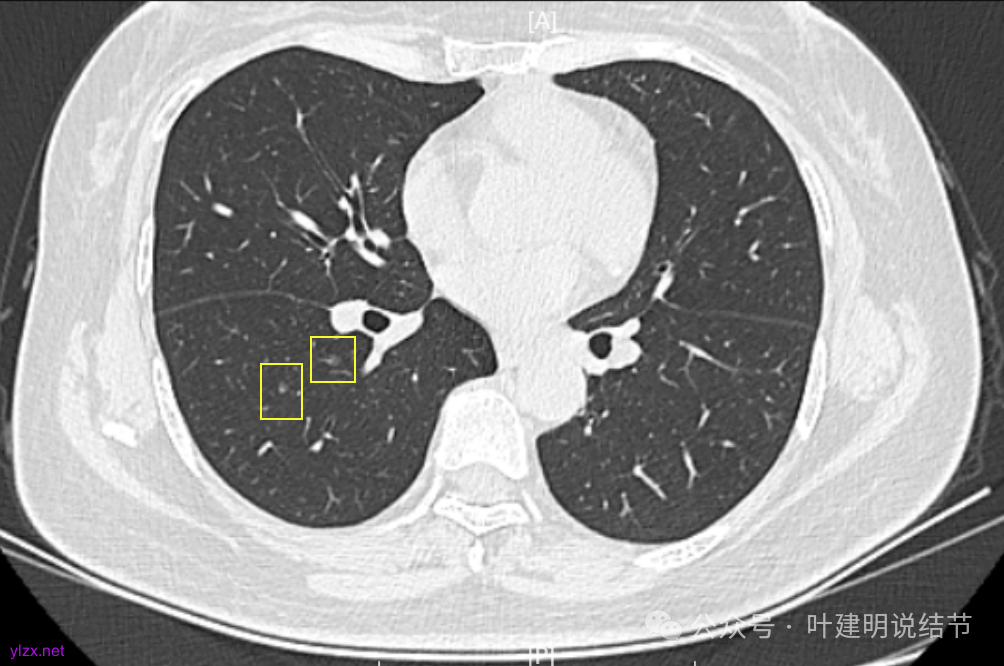

12.2025年4月复查,显示最大结节0.9*0.7。 另外,看几次报告,多发磨玻璃结节数量在上升,从2022年的3个到2025年的7个。

两肺多发磨玻璃结节,主病灶混合密度且有小血管进入,表面不平有毛刺,考虑微浸润性腺癌或浸润性腺癌可能性大,其余部分考虑原位癌或微浸润性腺癌,部分考虑肺泡上皮增生或不典型增生可能。总体上对比2022年说不上太明显的进展。但对于是否手术来讲,我仍倾向当年的意见,左侧的可以考虑近期亚肺叶(个人倾向楔切)切除,右侧的先随访,以后有进展并风险增加再考虑干预处理。因为要拉长两次手术的间隔,这样对机体的创伤与恢复更加有利一些。若定要仍不开刀,则建议要4-6个月复查,不过个人不太主张过于保守随访,对于像主病灶这种有少许实性成分的,不能保证肯定安全。意见供参考!